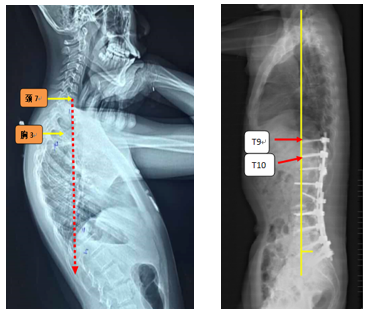

(2)上固定椎在交界区或存在交界性后凸

图6 长节段融合固定上固定椎(UIV)选择在胸10-12胸腰椎交界区是PJK的风险因素之一

图18 固定近端交界性后凸角>5°

A:术前固定近端交界性后凸角>5°;B:上固定椎未跨过此区域;C:术后随访出现PJK

Ø 颈7铅垂线距离UIV太远

图19 颈7铅垂线距离UIV太远